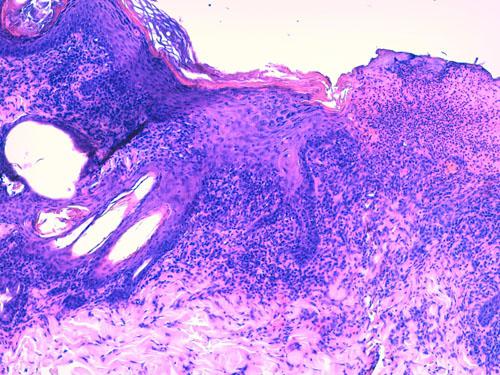

Des biopsies cutanées sont réalisées, et aucune autre antibiothérapie complémentaire n’est débutée dans l’attente des résultats. L’examen histopathologique révèle, des corps apoptotiques (kératinocytes nécrosés) sont observés au sein des couches épidermiques et dans la gaine folliculaire externe pilaire (photos 4 et 5). Des images de satellitose lymphocytaire sont présentes autour d’eux ainsi qu’une vacuolisation hydropique sous-épidermique multifocale (Photo 6). Par ailleurs, il est observé une dermatite d’interface lichénoïde marquée avec lymphocytes, de plus rares plasmocytes, des cellules présentatrices d’antigènes et des mélanophages (discrète incontinence pigmentaire) (Photo 7). Cet infiltrat lichénoïde forme également des manchons péri-annexiels. Le cycle pilaire est normal, et aucun élément figuré parasitaire ou fongique n’est noté.

cas-de-toxidermie-chez-bichon5Photo 4 et 5 : (HE*400, vue rapprochée) : 3 corps apoptotiques (kératinocytes nécrosés)

au sein des couches épidermiques, image de satellitose, infiltrat lichénoïde marqué